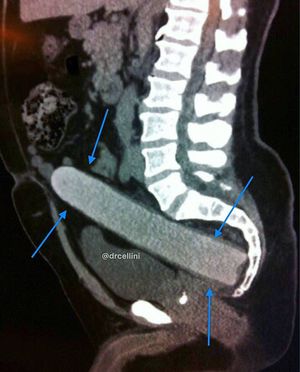

What do you think the foreign object was?????? And in what location??? Hint: Ewwwww😱😂😂😂 Comment below and Tag a friend!👇

Dildo/vibrator

Dildo anal canal I may assume it is a male du to urethra and believe to be prostate